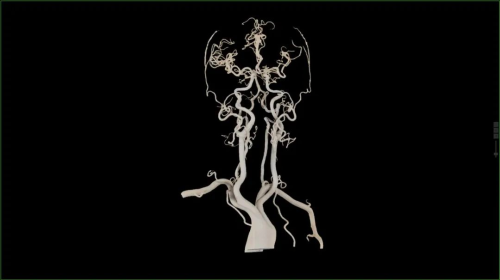

在卒中救治领域,无极系列CT配备的16cm宽体探测器,无需移床即可覆盖全脑,能够快速判断卒中类型。得益于该设备的协议快速切换能力,支持在缺血性脑卒中患者全脑灌注扫描中插入头颈CTA协议,60秒内便能完成全脑CTP+头颈CTA+全脑CTP的一站式扫描,一次操作即可采集全脑灌注数据及头颈CTA图像,获取包括脑实质解剖成像、脑血管及脑血流分布在内的全脑信息,大幅缩短了检查时间,让卒中救治分秒必争。

头颈CTA